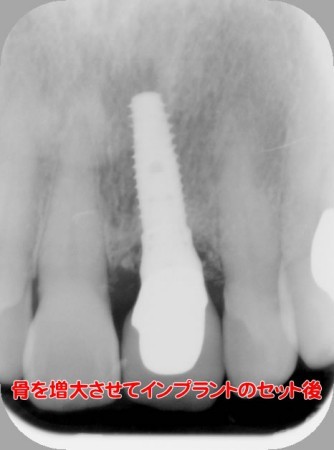

インプラントの術前・術後 Nさん